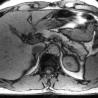

Herz, Leber, Gallenwege, Bauchspeicheldrüse, Nieren, Harnwege, Geschlechtsorgane